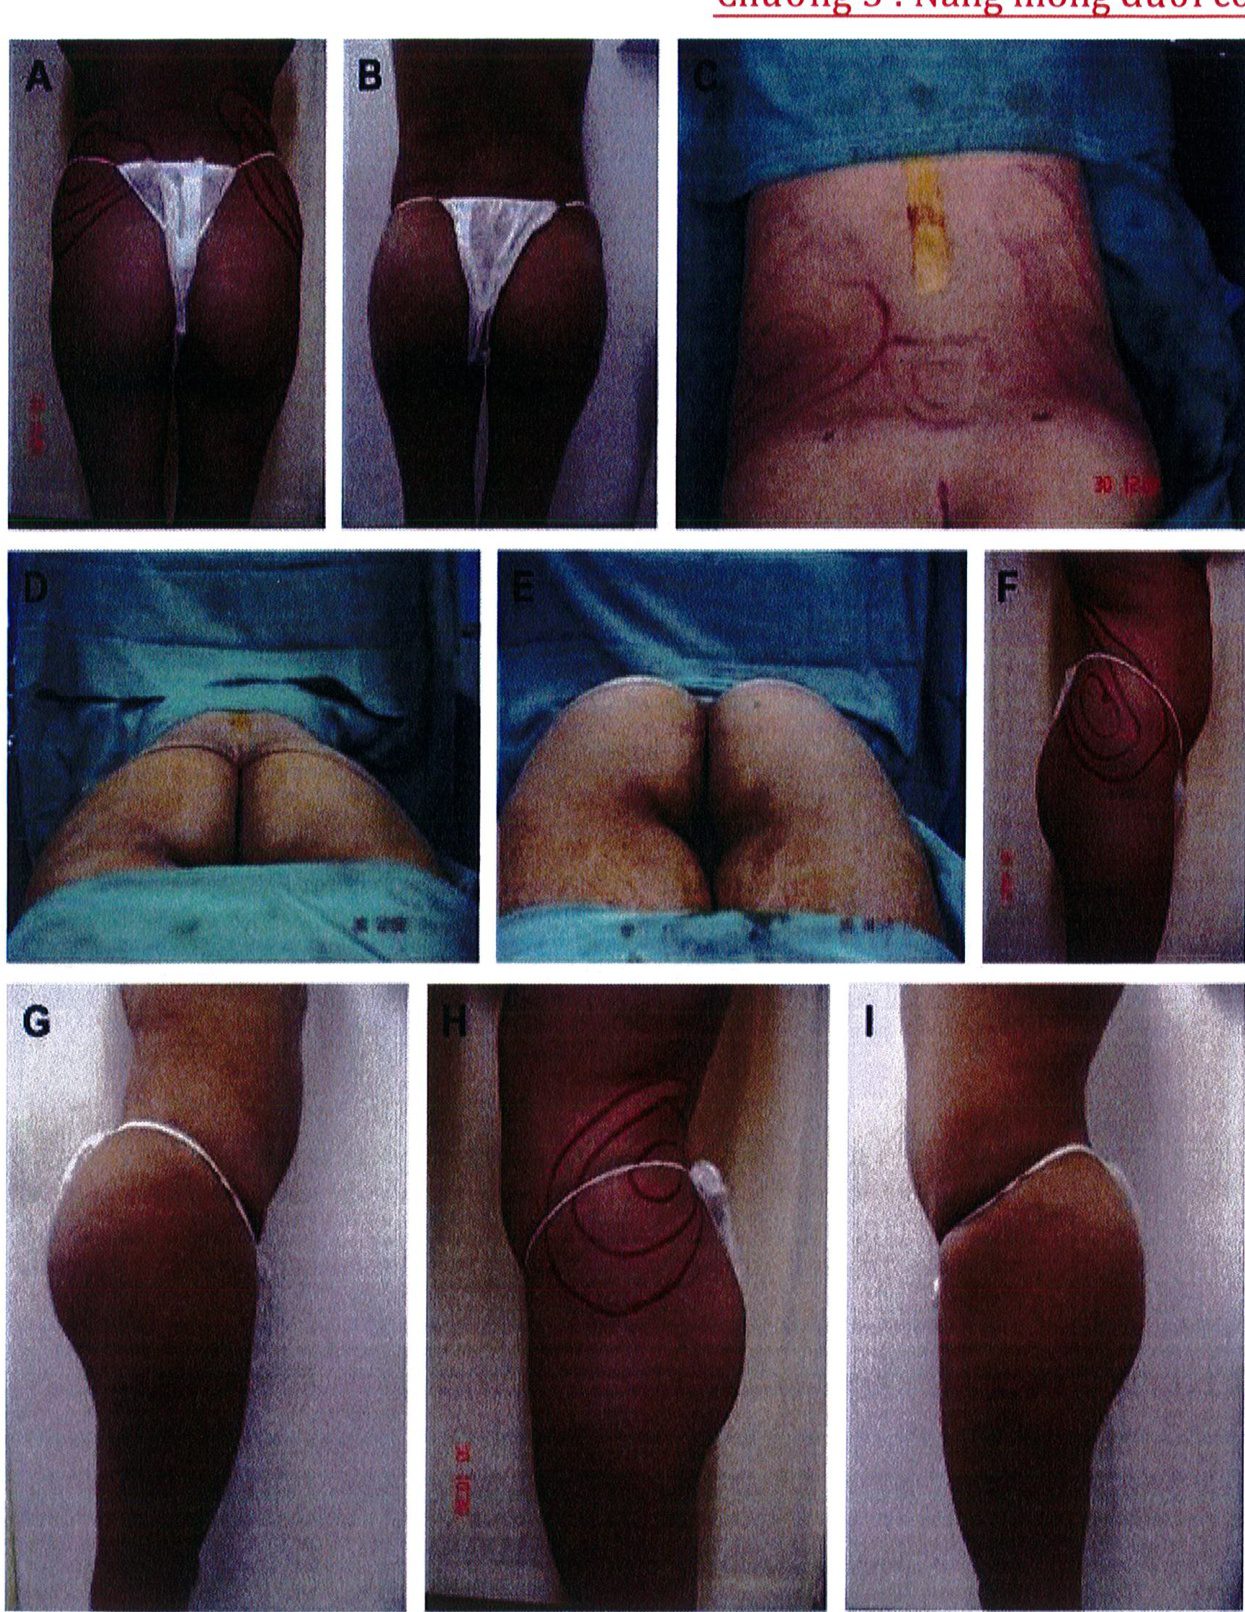

Hình. 3. (A-H) Tiền phẫu, chu phẫu và sau hậu phẫu 6 tháng của một bệnh nhân nữ 38 tuổi đươc ghép túi đôn mông với thể tích 330 cm3.

Chương 5 : Nâng mông dưới cơ

Hình. 4. (A-I) Hình ảnh tiền phẫu, chu phẫu và sau hậu phẫu 11 tháng của một phụ nữ 25 tuổi đã được thực hiện hút mỡ vùng éo, hông và sau xương vùng, đồng thời ghép khối cấy thể tích 270cm3.